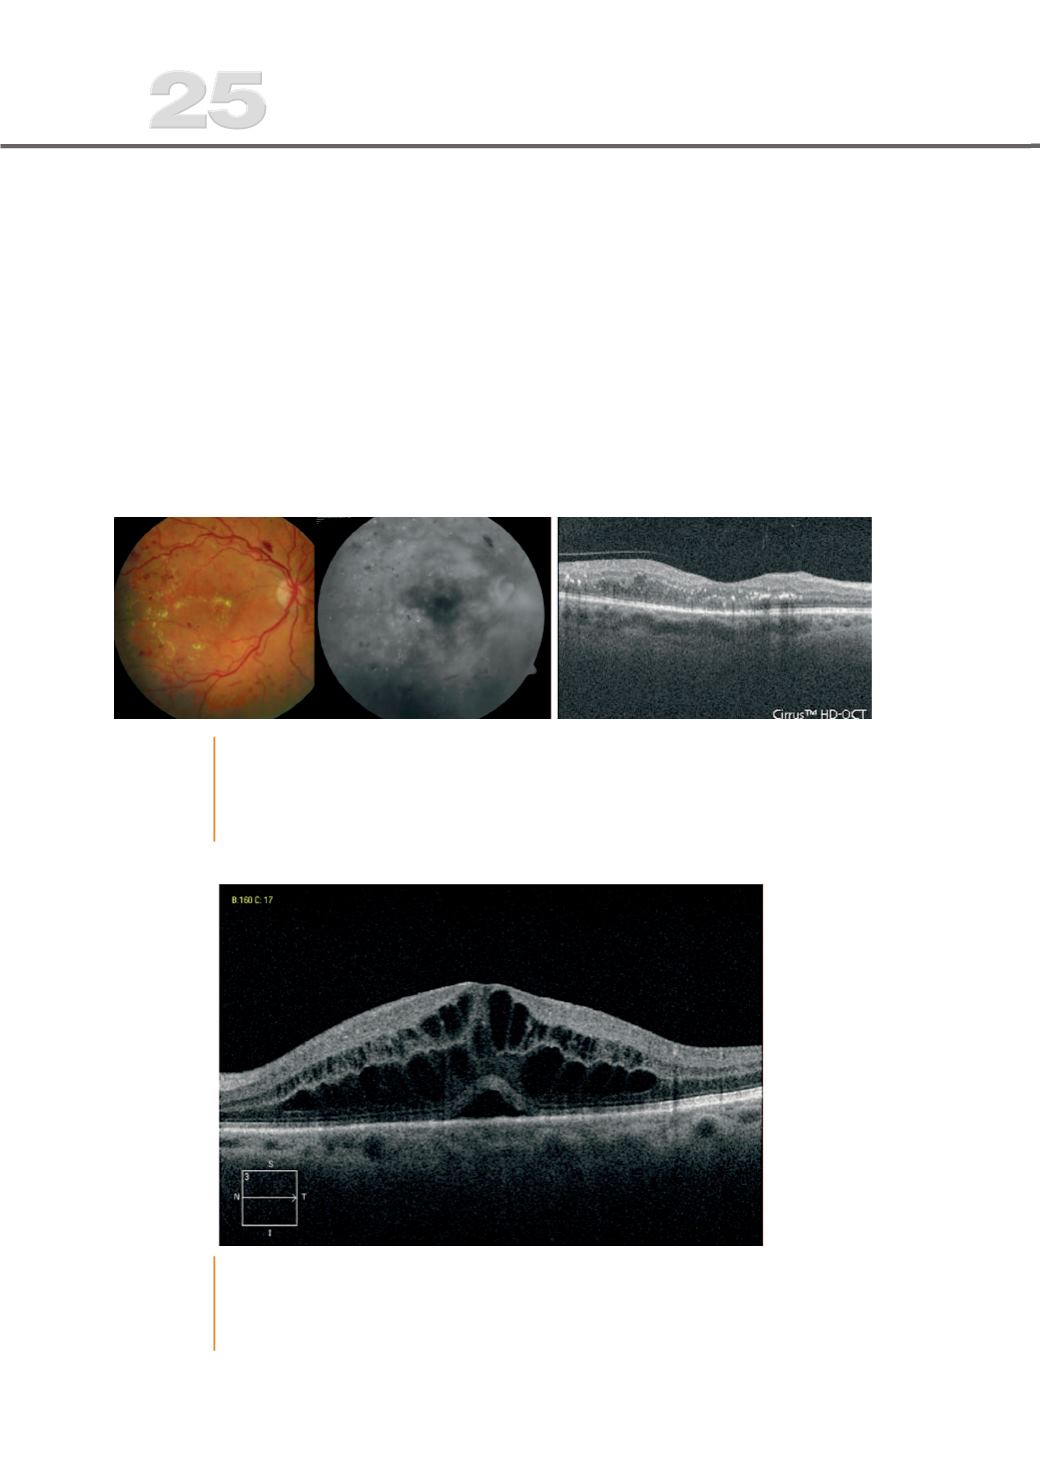

Fig. 1

EMD em que na retinogra%a e angiogra%a se visualizam lesões de RD como

hemorragias, exsudados, derrame difuso, e no OCT alguns quistos, pontos

hiperre`etivos correspondentes a hemorragias e exsudados, desorganização

moderada das camadas e atro%a da camada de fotorreceptores e EPR.